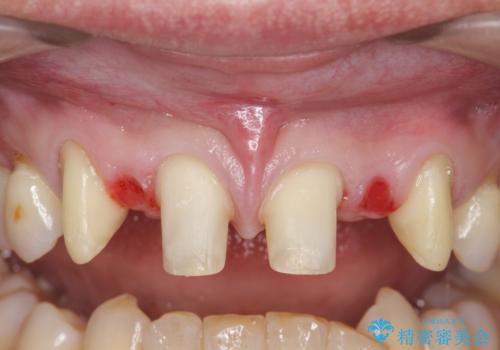

- 前歯部のすきっぱと歯並びが気になるので診て欲しいといらっしゃった方の症例です。

全顎矯正は御希望されなかったため、上顎前歯部のみの部分矯正とオールセラミッククラウンによる補綴を行いました。

- オールセラミッククラウン…¥100,000×6、仮歯…¥10,000×6、部分矯正…¥200,000費用は治療当時の料金となります